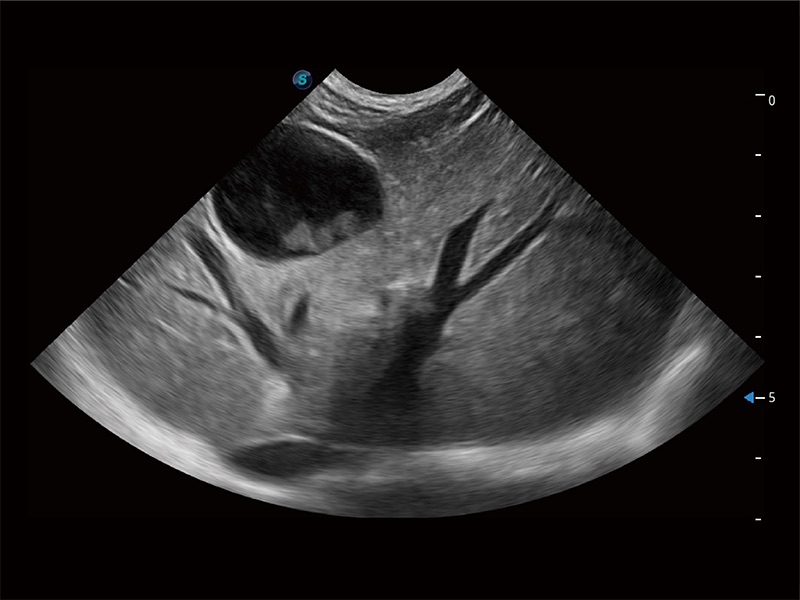

ProPet 80 配備了豐富的心臟探頭群、先進(jìn)的成像技術(shù)和專業(yè)的心臟測(cè)量工具,可幫助動(dòng)物醫(yī)生為不同體型和生理結(jié)構(gòu)的動(dòng)物提供心臟和心肌功能的全面評(píng)估。

ProPet 80 全新的動(dòng)物超聲智能軟件和豐富的探頭群,為動(dòng)物醫(yī)生提供了高清晰度和精細(xì)分辨率的圖像,無(wú)論在寵物、馬科、畜牧還是實(shí)驗(yàn)室動(dòng)物等應(yīng)用中都可以輕松應(yīng)對(duì),為您的日常工作帶來(lái)滿意的體驗(yàn)。